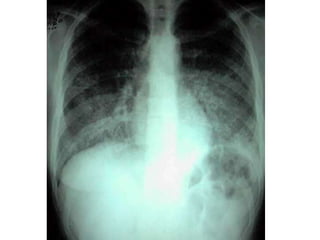

SDRALPA (Lesão Pulmonar Aguda):

Início agudo

PaO2/FiO2: 200-300 (apesar do uso de PEEP)

Rx Tórax: Infiltrados alvéolo-intersticiais, micro ou macronodulares, bilaterais e assimétricos